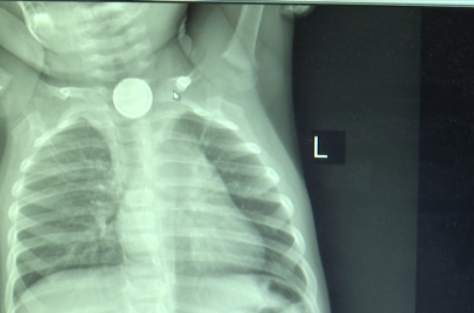

開遠1歲小孩誤吞電池 食道被嚴重灼傷